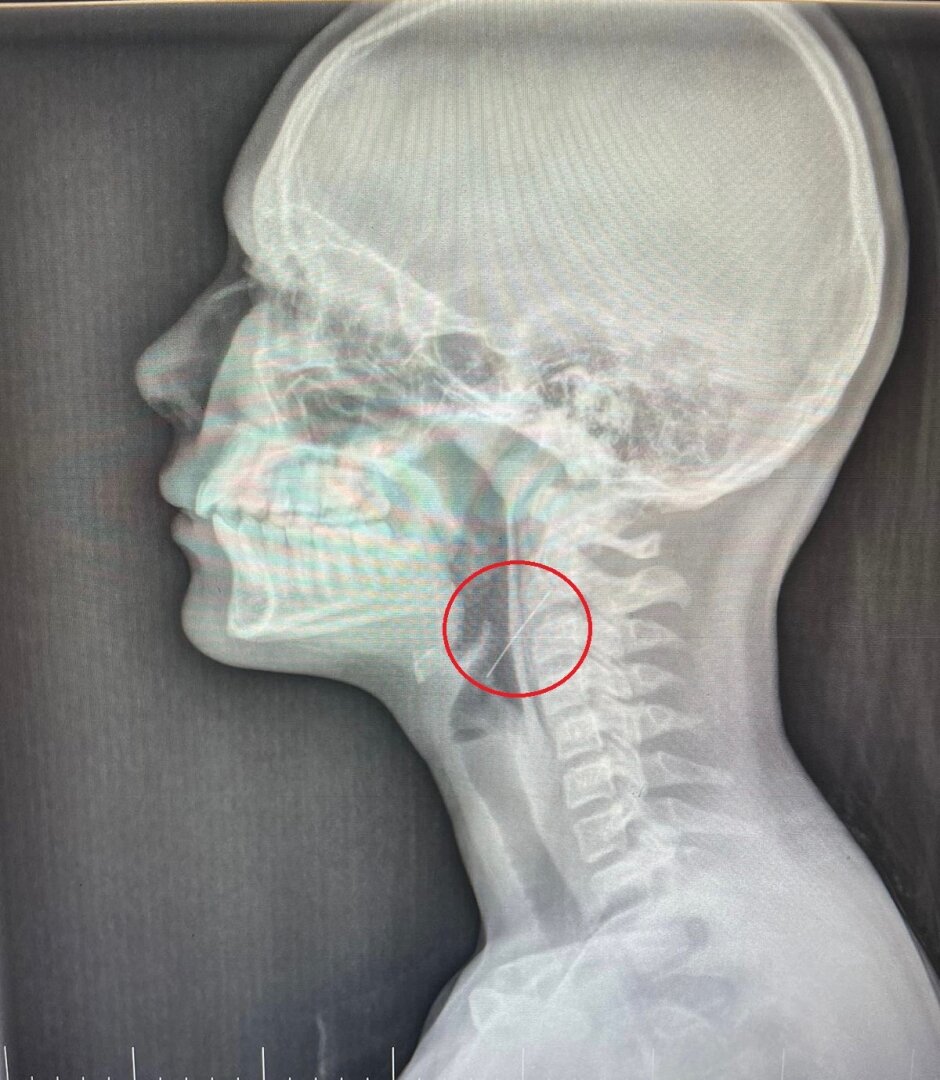

Девочка проглотила иголку, наряжая гирляндой новогоднюю ёлку

Девочку доставили в детскую больницу №1 столицы Черноземья. На протяжении ночи бригада хирургов проводила операцию по извлечению инородного предмета. Во время прямой ларингоскопии удалось найти иголку — они попала в правую стенку глотки. Ее успешно достали.